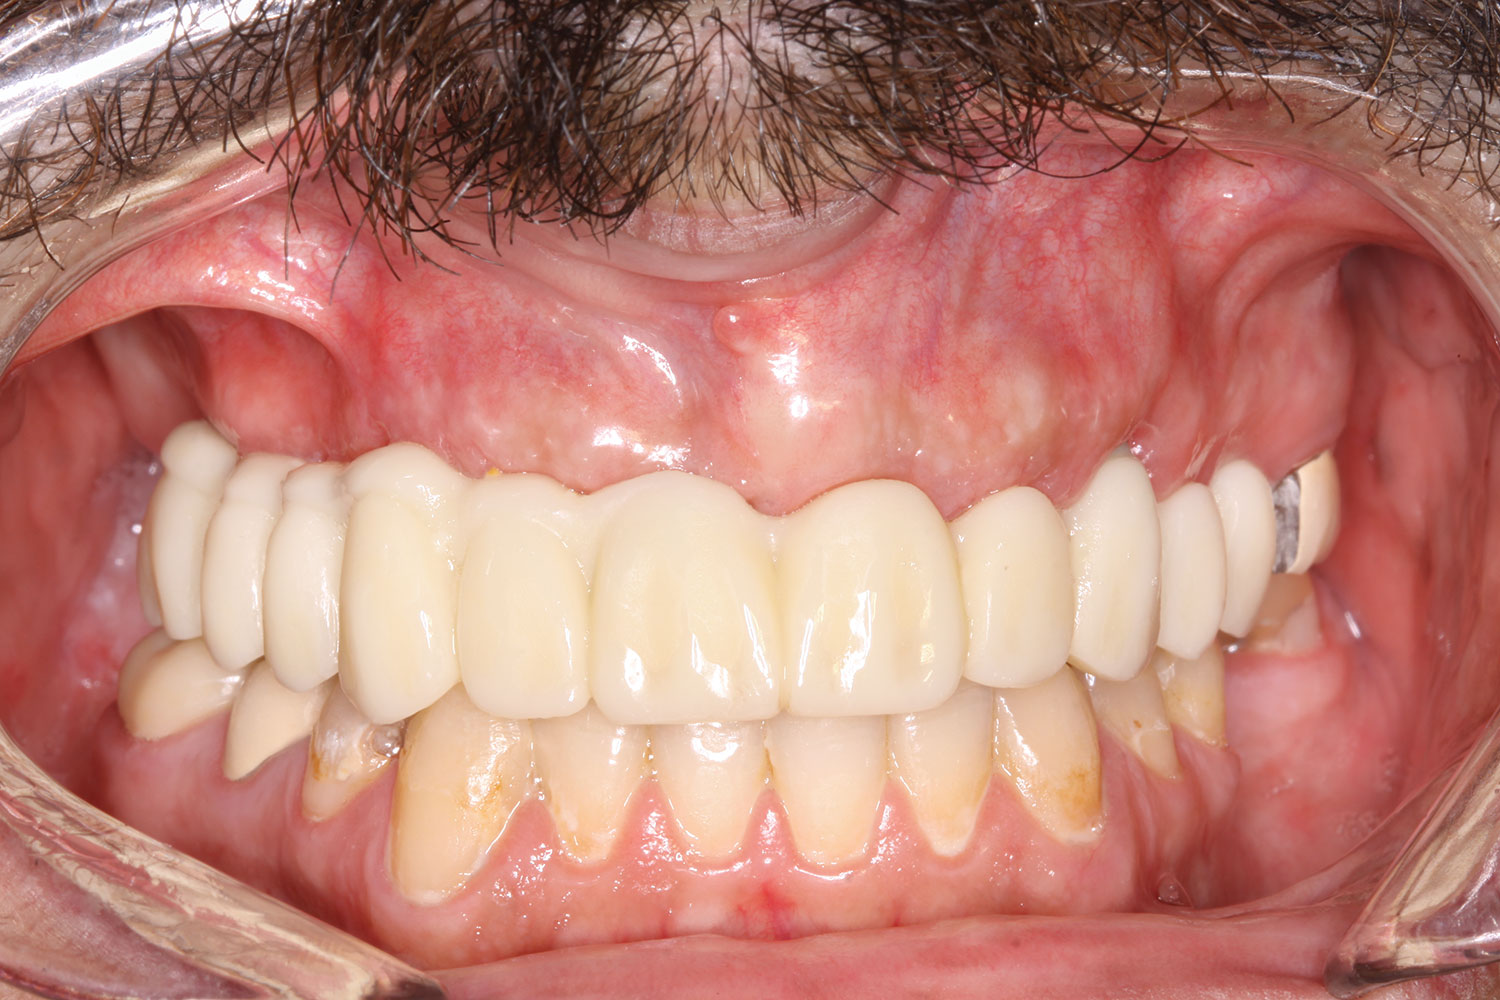

Case 3

A 67-year-old female patient presented with a highly compromised maxillary and mandibular dentition, including teeth Nos. 2 through 15, 17, 21 through 24, and 27 through 30. Soft tissues were of normal contour, and bone profiles were generally sustained and favorable. The patient was excited about the prospect of transforming both her maxillary and mandibular compromised esthetics and function in one visit. (Case 3 is depicted in Figure 23 through Figure 42.)

The completed prosthesis was then screwed directly onto the multi-unit abutments with Rosen screws with no ti-bases and torqued to 20 Ncm. Screw-access holes were filled, and no occlusal adjustment was necessary. The fit of the prosthesis was precise and stable and the phonetics of the patient was ideal. The patient was overwhelmed by the significant esthetic improvement with this set of teeth in place.

Fig 38. Maxillary and mandibular provisional restorations inserted, day of surgery.

Figure 38